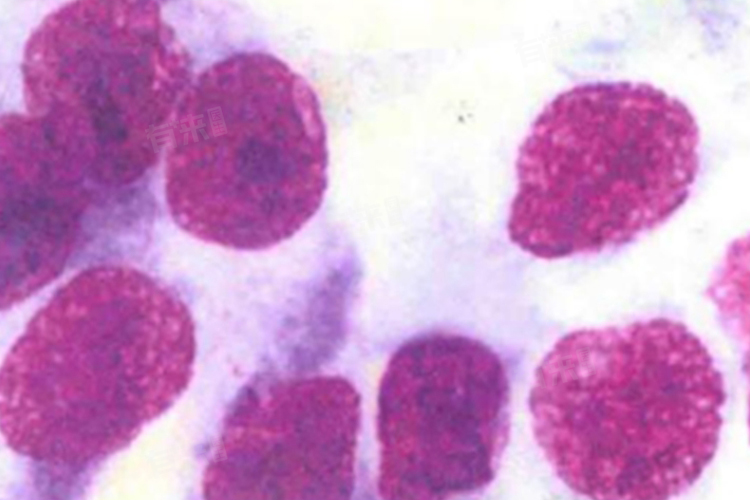

- 高中分化腺癌这一术语主要描述的是癌细胞的分化程度,即癌细胞的形态和功能与正常细胞相似的程度。其中,高分化腺癌的癌细胞分化程度较高,形态和功能更接近正常细胞,恶性程度相对较低;而中分化腺癌的癌细胞分化程度中等,恶性程度介于高分化和低分化之间。